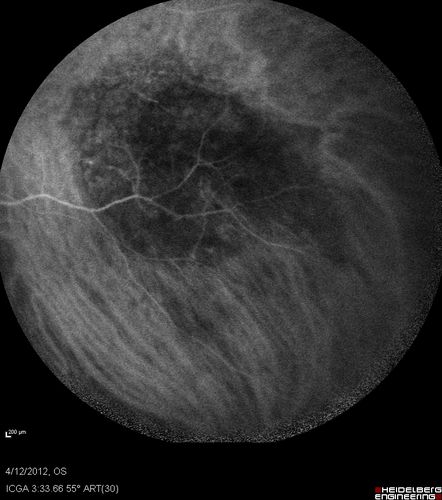

Medium Choroidal Melanoma Left Eye

Melanoma - Choroidal Medium - Macular